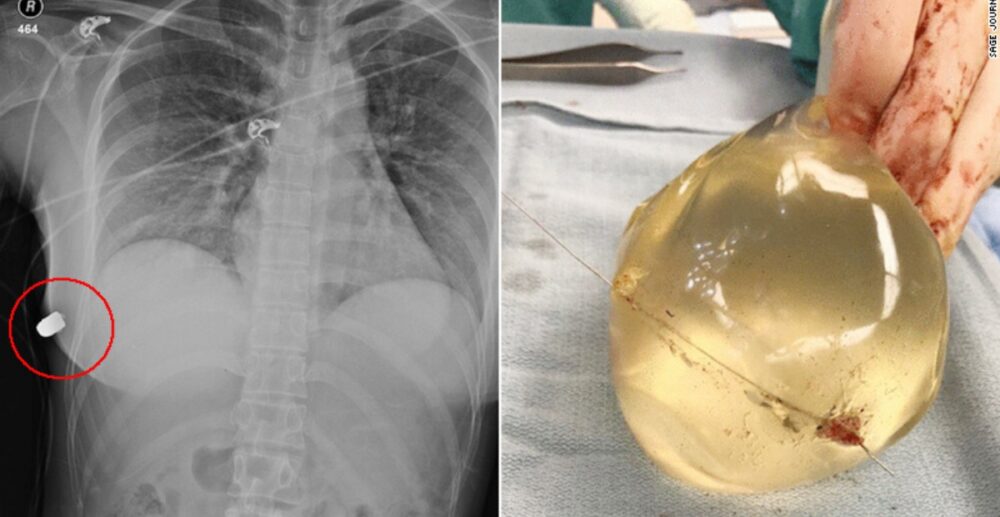

រូបភាព X-ray ដើមទ្រូងរបស់ស្ត្រីរងគ្រោះ បានបង្ហាញឱ្យឃើញនូវគ្រាប់កាំភ្លើងកប់ជាប់នៅនឹងផ្ទាំងកំពែងខាងឆ្វេងនៃដើមទ្រូងដែលជាដុំស៊ីលីខូន គឺជាដុំស៊ីលីខូនដែលបានទទួលការអនុញ្ញាតឱ្យដាក់លក់នៅក្នុងសហរដ្ឋ អាមេរិក ចំនួន 2ប្រភេទ ដែលសុទ្ធតែជាប្រភេទមានសម្បកហ៊ុមព័ទ្ធ ដែល 1ប្រភេទមានទឹករ៉ែនៅខាងក្នុង និង 1ប្រភេទទៀតមានជេលនៅខាងក្នុង។

“គ្រាប់កាំភ្លើង បុកចូលទៅរកដើមទ្រូងខាងឆ្វេង តែធ្វើឱ្យទៅកើតមានស្នាមប្រេះបែករបស់ឆ្អឹងជំនីផ្នែកខាងស្ដាំ។ លក្ខណៈគ្រាប់កាំភ្លើង បានបុកទម្លុះស្បែក ហើយខ្ទាតត្រឡប់មកក្រោយ ឆ្លងកាត់ឆ្អឹងសន្ទះទ្រូង តម្រង់ទៅដើមទ្រូងផ្នែកខាងស្ដាំ។ ដុំស៊ីលីខូនដែលបង្កើនទំហំសុដន់ ធ្វើឱ្យគ្រាប់កាំភ្លើងប្ដូរទិសដៅ”

លោកវេជ្ជបណ្ឌិត ម៉េកអ៊ីវេនីវ បានថ្លែងទៀតថា ស្ត្រីរងគ្រោះមានស្នាមរបួសដោយគ្រាប់កាំភ្លើង បែកឆ្អឹងជំនី និងបែកដុំស៊ីលីខូន តែអវយវៈផ្សេងទៀត គ្មានរងការខូចខាតអ្វីទាំងអស់ និងនៅពេលមើលតាមជ្រុងនៃការវះកាត់ យើងឃើញថា គ្រាប់កាំភ្លើងត្រូវបានបង្វែរទិសដៅដោយសារដុំស៊ីលីខូន។